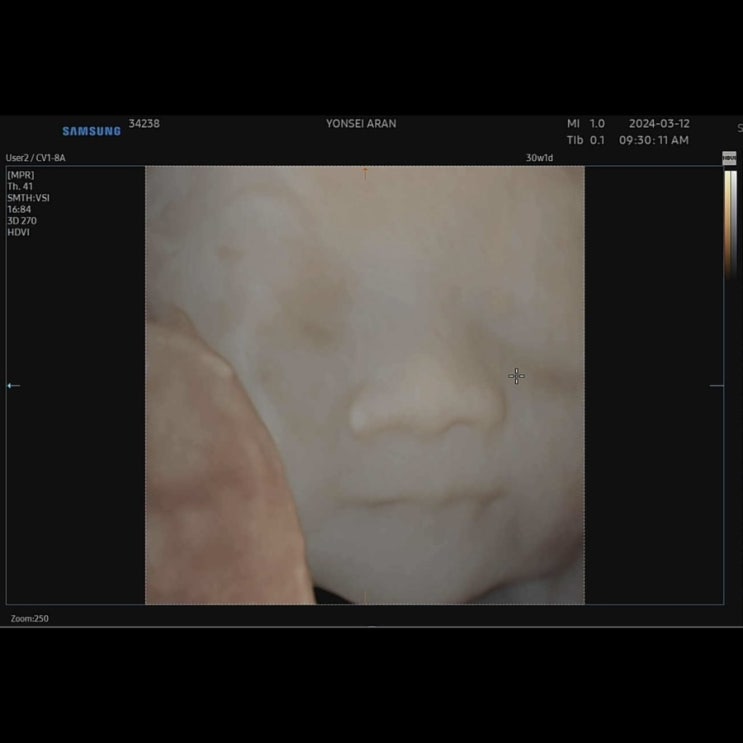

[임신후기] 30주 입체초음파 아기빨래 정리하는일상

이제 임신후기가 되니, 몸도 무거워지고 할 일이 더 많아지면서 바빠지네요. 초기,중기 때 신경쓰지 못했던...